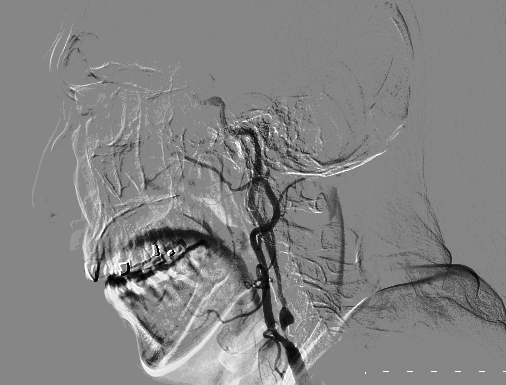

DSA显示:右侧颈总颈内动脉重度狭窄。